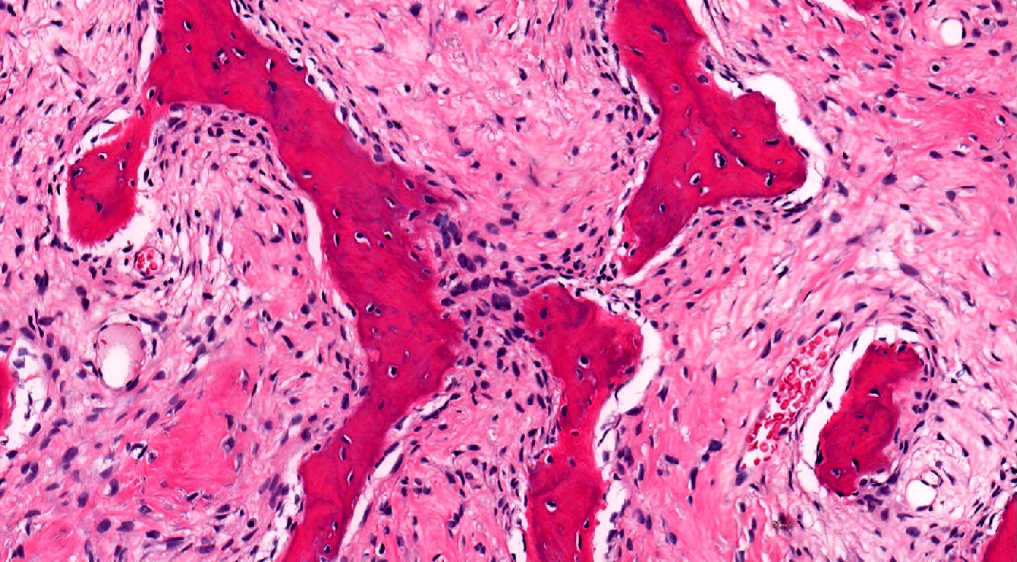

Microscopic (histologic) description

- Branching and anastomosing irregular trabeculae of woven bone ("C" and "S" shapes) with no conspicuous osteoblastic rimming

- No / rare osteoclasts

- Intervening fibrous stroma containing cytologically bland spindle cells, without prominent cytologic atypia

- Mitotic figures rare

- Stromal changes, including myxoid change and fatty metaplasia, may be seen in some cases (BMC Musculoskelet Disord 2003;4:20)

- Secondary aneurysmal bone cyst-like changes may also be seen (Turk Patoloji Derg 2018;34:234)

- Fibrocartilaginous dysplasia: uncommon variant containing variable proportions of cartilaginous differentiation and enchondral ossification (Am J Surg Pathol 1993;17:924)

- Growing collagen (Sharpey's fibers) may form perpendicular to the sites of bone formation but are not essential for diagnosis (Oral Dis 2017;23:697)

Microscopic (histologic) images